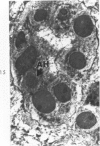

Liver biopsies obtained from 24 patients with alcoholic liver disease were studied by light and electron microscopy. Comparisons of the same cells in adjacent sections revealed that alcoholic hyalin is a fibrillar deposit without limiting membranes and is readily distinguished from giant mitochondria. This characteristic fibrillar structure was encountered in hepatocytes, ductular cells and in benign and malignant hepatomas. Three distinct morphologic forms of alcoholic hyalin were observed: a) bundles of filaments in parallel arrays, b) clusters of randomly oriented fibrils and c) a granular or amorphous substance containing only scattered remains of fibrils. Closely associated with alcoholic hyalin and often found along its entire circumference, were bundles of fine filaments in parallel arrangement of much smaller size. These occasionally displayed variations in orientation and merged with the filaments in the alcoholic hyalin body. Similar fine filaments were observed, in considerable excess, in cells which did not contain alcoholic hyalin. According to our findings, the fine filaments and the significantly larger filaments in alcoholic hyalin could be parts of a contractile system elaborated by host cells during the course of hepatic injury.